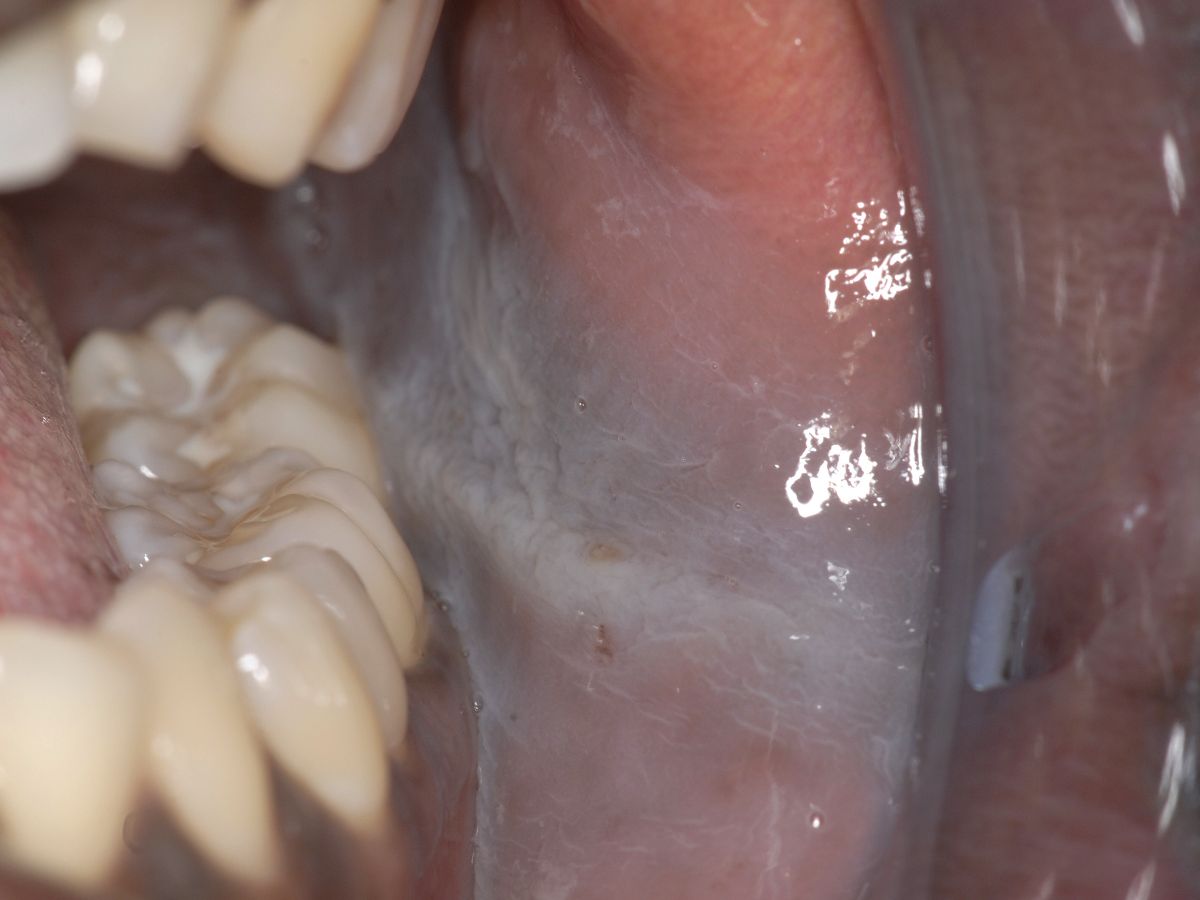

bijten waardoor een streep zichtbaar kan zijn precies ter

hoogte van het bijtvlak, die de

linea alba (mucosa)

![Linea alba mucosa (click on photo to enlarge) [source: www.huidziekten.nl] Linea alba mucosa](../../../images/linea-alba-mucosa-1z.jpg) |

linea

alba mucosa |